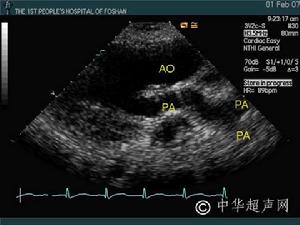

4.超聲心動圖左房粘液瘤在左心腔內見到異常的點片狀反射光團,活動於左房、左室之間,收縮期回到左房腔,舒張期達二尖瓣口進入左室,二尖瓣前葉EF斜率減低,左房增大。右房粘液瘤異常反射光團在右心腔內,收縮期在右房,舒張期隨三尖瓣向右室方向移動或通過三尖瓣口進入右室腔。右房、右室增大。

3.超聲心動圖檢查顯示瘤體隨心臟收縮和舒張活動。心血管造影顯示心腔內占位性病變,但有一定的假陽性、自有超聲心動圖,心血管造影較少套用。